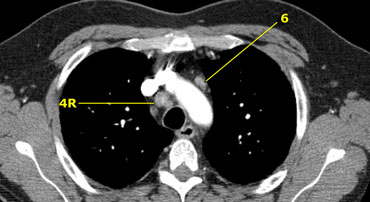

4R. Hạch cạnh dưới phải khí quản.

Bờ trên: chỗ giao nhau của tĩnh mạch vô danh với khí quản.

Bờ dưới: bờ dưới của tĩnh mạch Azygos.

Hạch ở nhóm 4R, và cũng có hạch ở bên quai động mạch chủ (nhóm 6)

6. Hạch ở cạnh động mạch chủ (Para-aortic)

Hạch ở trước và bên động mạch chủ lên và quai động mạch chủ

6. Hạch cạnh động mạch chủ

Nằm ở phía trước và phía bên của động mạch chủ lên và quai động mạch chủ từ bờ trên đến bờ dưới của quai động mạch chủ.